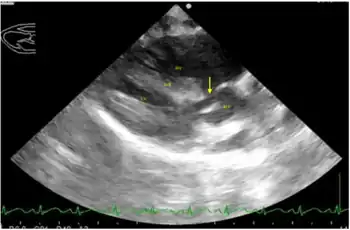

An overriding aorta is a congenital heart defect where the aorta is positioned directly over a ventricular septal defect (VSD), instead of over the left ventricle.[1] The result is that the aorta receives some blood from the right ventricle, causing mixing of oxygenated and deoxygenated blood, and thereby reducing the amount of oxygen delivered to the tissues.

It is one of the four findings in the classic tetralogy of Fallot. The other three findings are right ventricular outflow tract (RVOT) obstruction (most often subpulmonary stenosis), right ventricular hypertrophy (RVH), and ventricular septal defect (VSD).